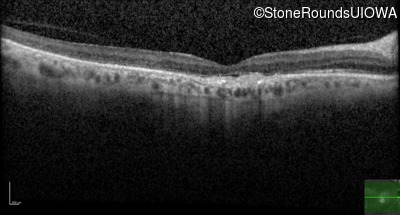

Optical Coherence Tomography - Right - 20/125 -2

Exemplar / OCT Stack